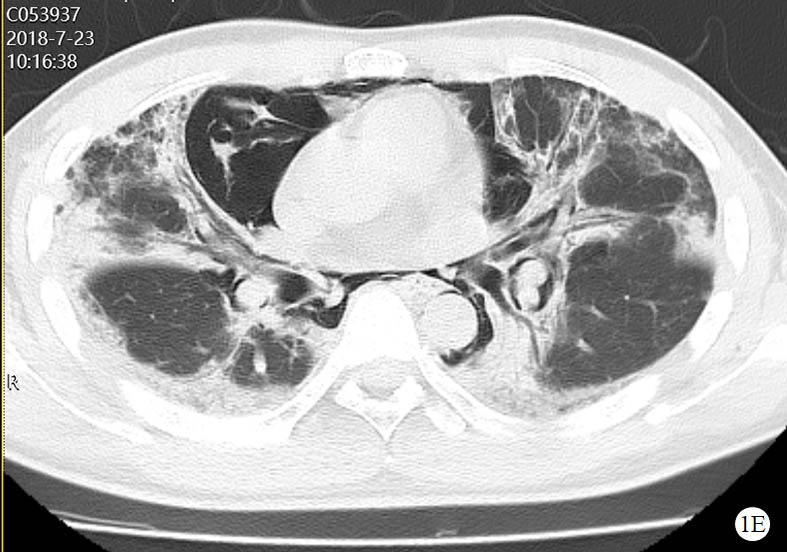

图 1 患者口服百草枯后胸部CT影像学变化

2018-07-23 CT图